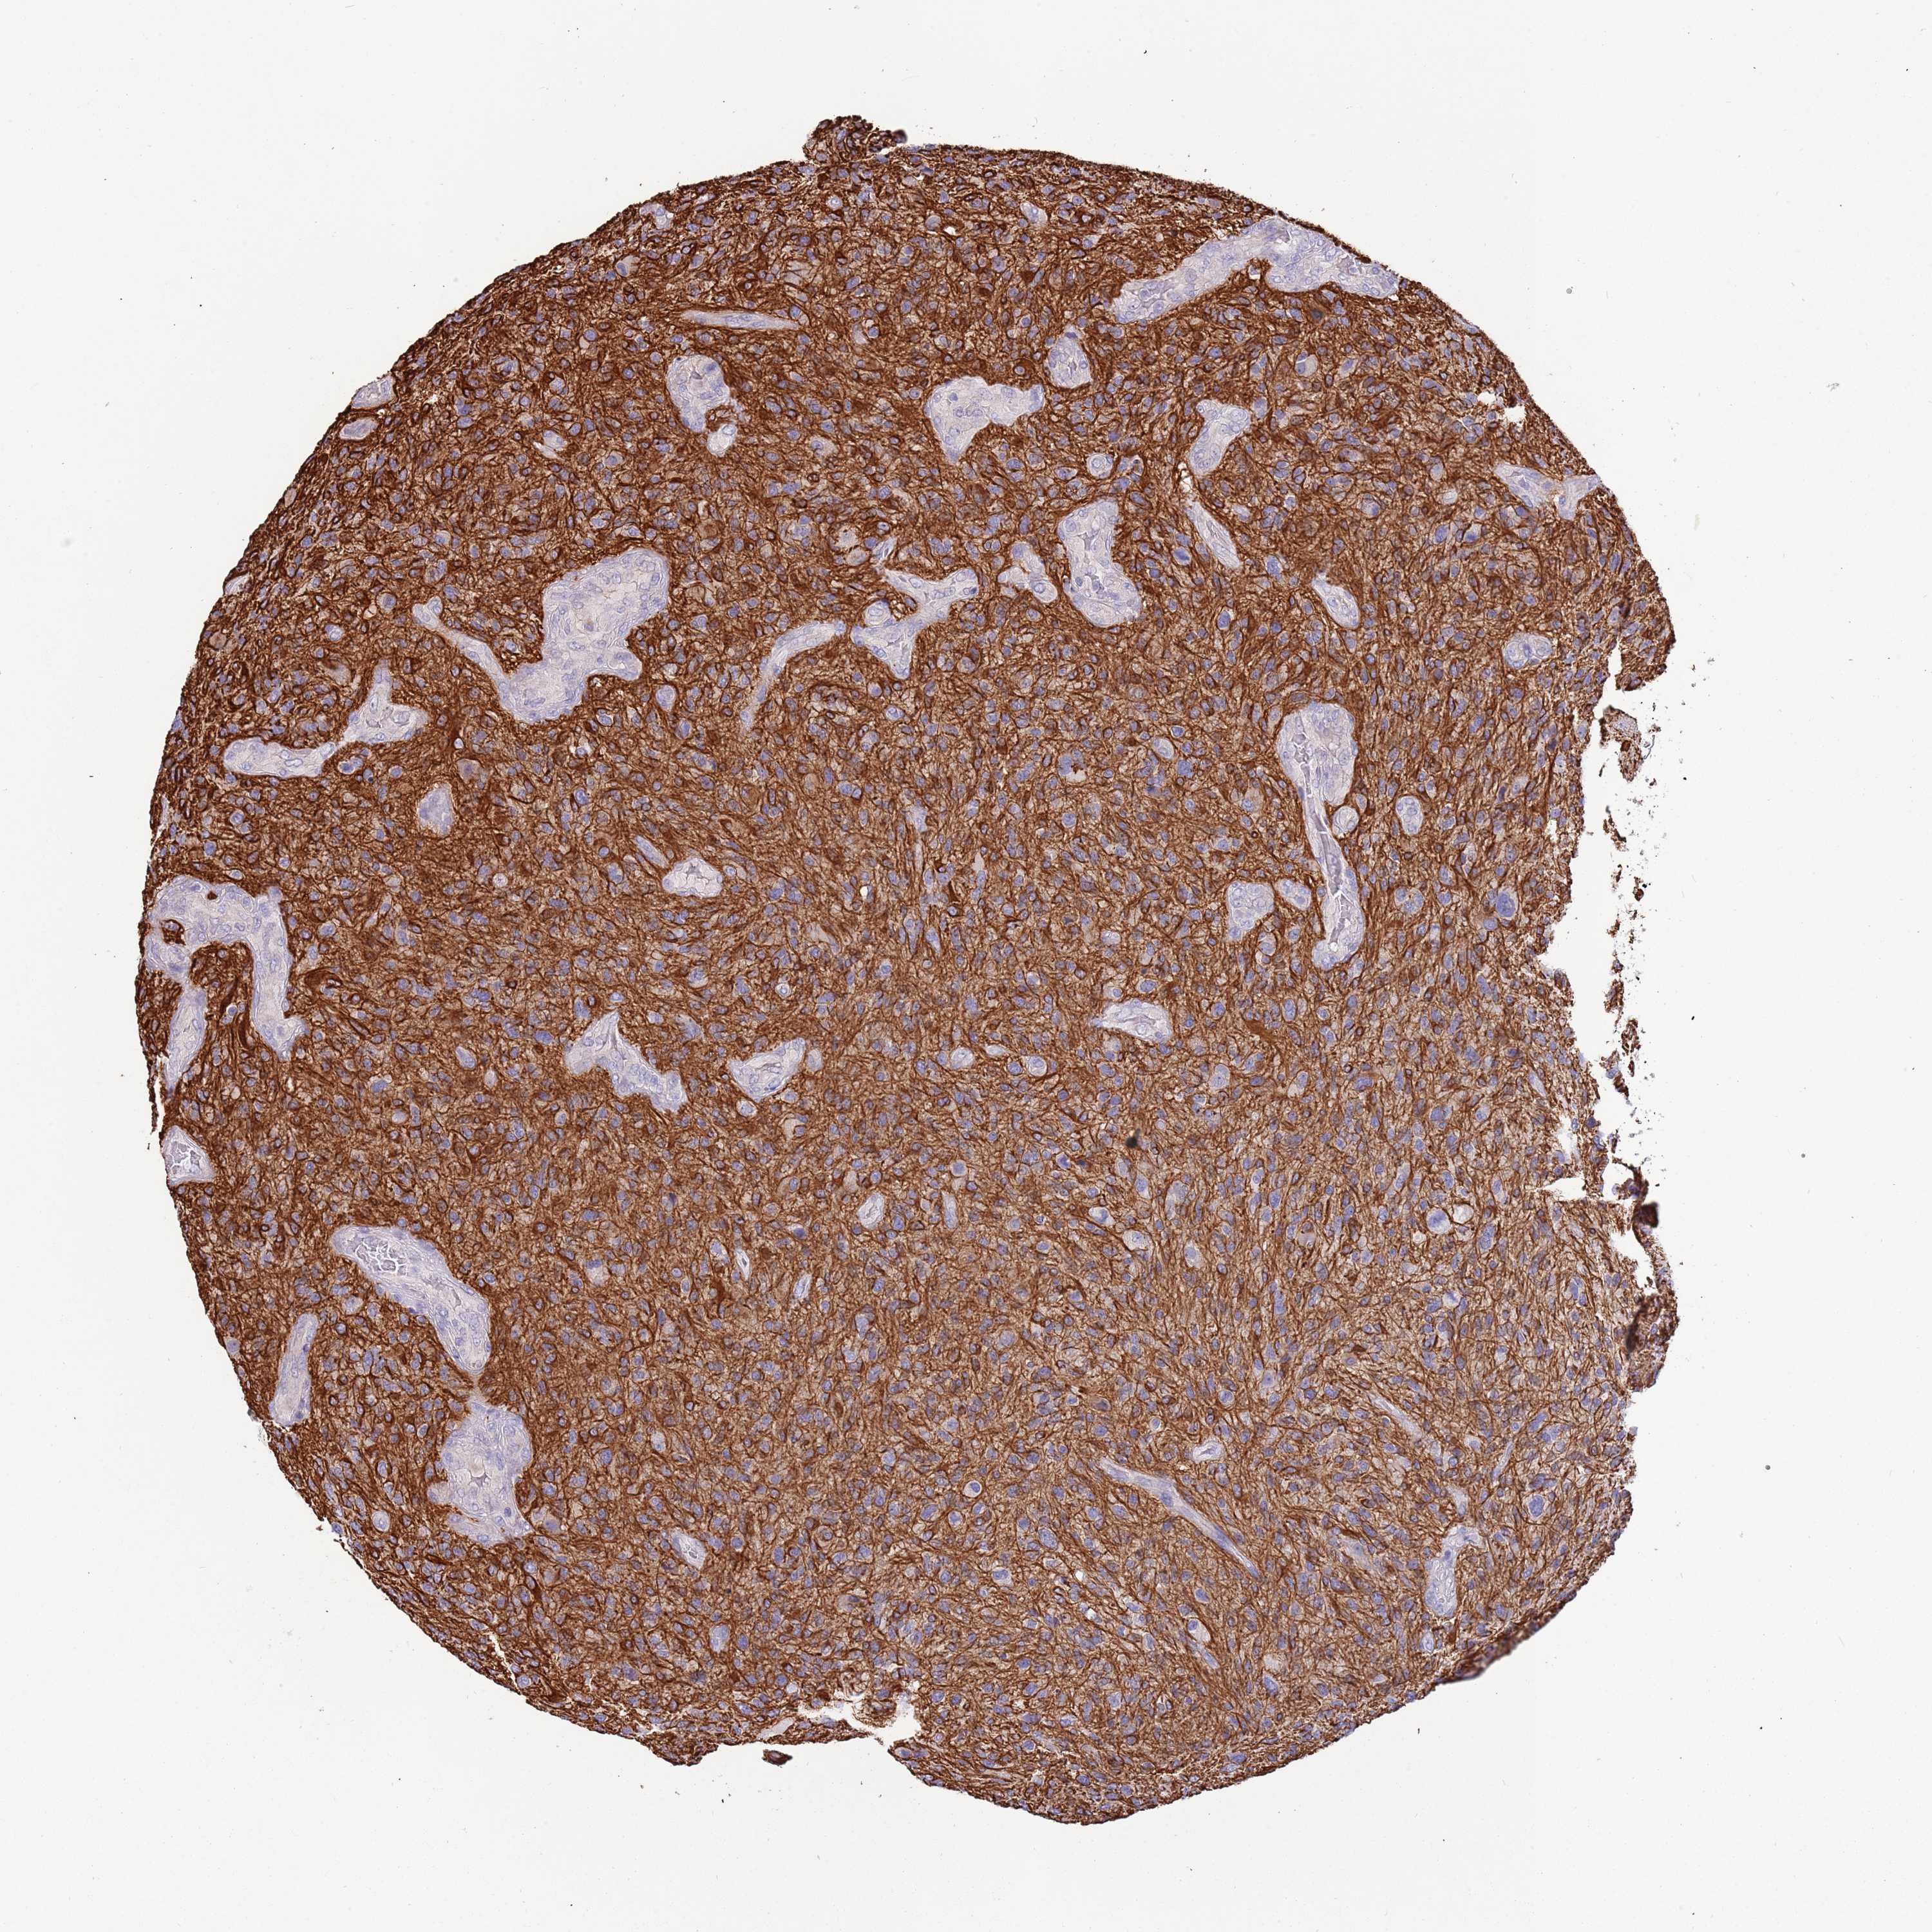

GLIOMA - Protein expressioni

A mouse-over function shows sample information and annotation data. Click on an image to view it in a full screen mode. Samples can be filtered based on level of antibody staining by selecting one or several of the following categories: high, medium, low and not detected. The assay and annotation is described here.

Note that samples used for immunohistochemistry by the Human Protein Atlas do not correspond to samples in the TCGA dataset.

Antibody stainingi

Antibody staining in the annotated cell types in the current human tissue is reported as not detected, low, medium, or high, based on conventional immunohistochemistry profiling in selected tissues. This score is based on the combination of the staining intensity and fraction of stained cells.

Each image is clickable and will lead to virtual microscopy that enables deeper exploration of all samples and also displays staining intensity scores, fraction scores and subcellular localization as well as patient and tissue information for each sample.

Antibody HPA040703

Antibody HPA047801

Staining

High

Medium

Low

Not detected

Intensity

Strong

Moderate

Weak

Negative

Quantity

>75%

75%-25%

<25%

None

Location

Nuclear

Cytoplasmic/membranous

Cytoplasmic/membranous,nuclear

Glioma, malignant, High grade

Glioma, malignant, Low grade